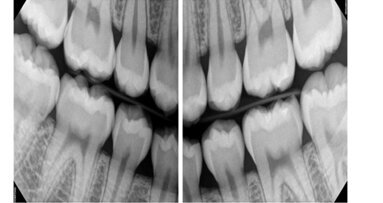

Enter DEXIS digital radiography. No more shelling out hard-earned revenue for processing supplies and hauling, and no more paying assistants to baby-sit the processor instead of establishing a rapport with the patients. When patients see the Platinum images of their teeth almost instantly on computer monitors, they will be impressed with the new technology, resulting in loyalty and new referrals.